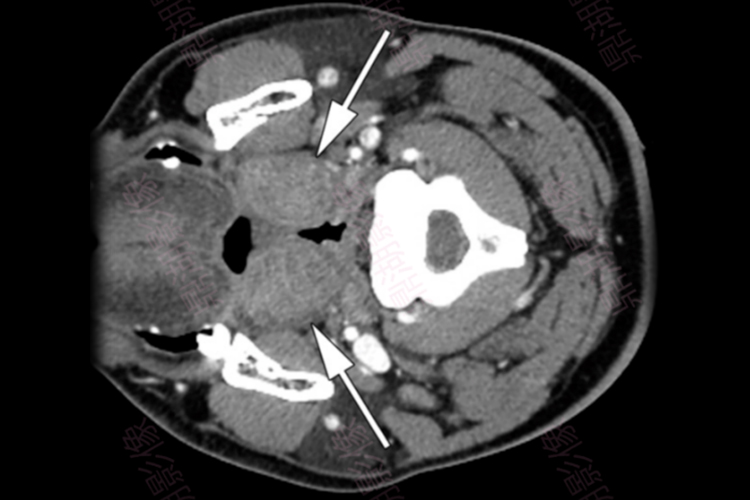

扁桃体炎:CT可见扁桃体区软组织广泛肿胀,密度欠均匀,边界不清,可有脓肿形成。肿胀软组织内出现低密度区,增强表现为边缘环状强化,中央低密度坏死,可累及咽后间隙、咽旁间隙及颌下间隙。